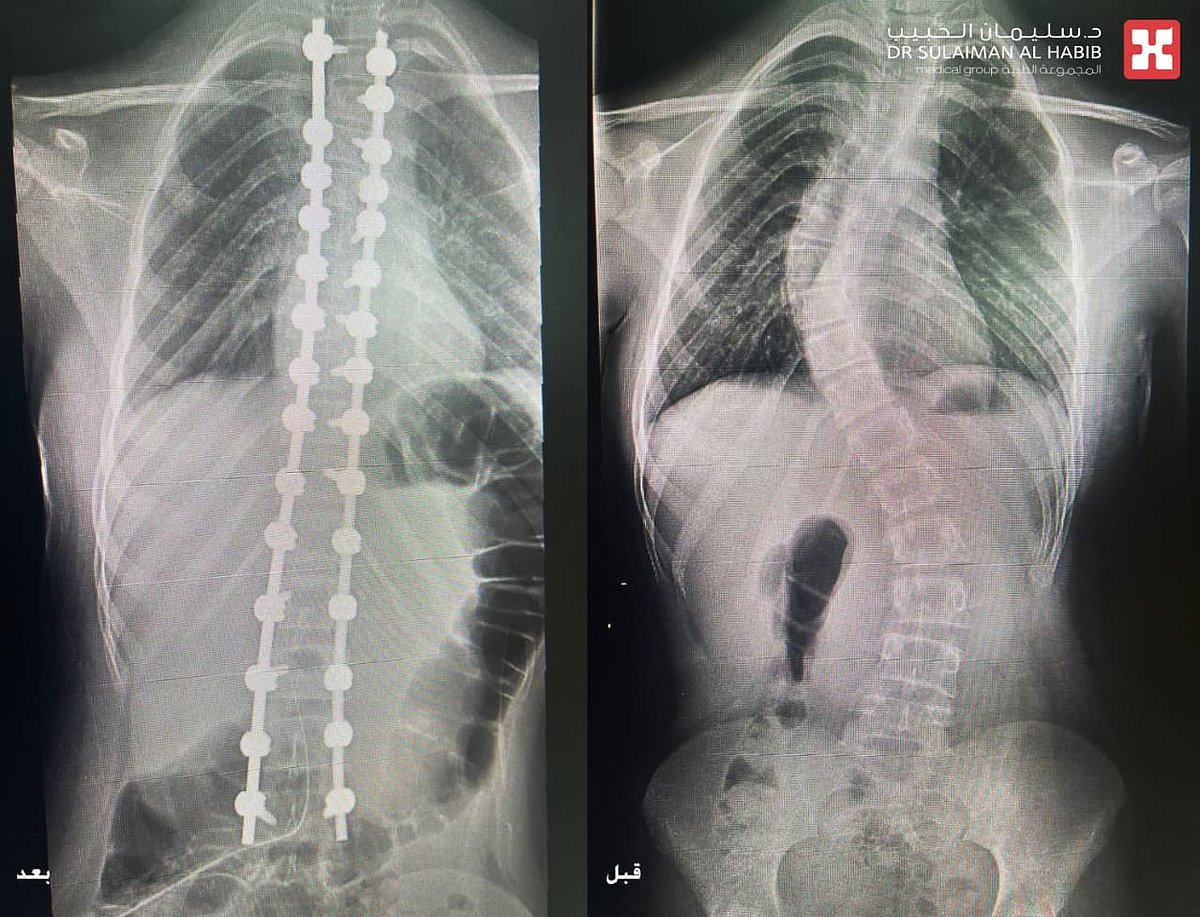

مجمع الدكتور سليمان الحبيب بالعليا يُنهي معاناة فتاة 13 عام مع الجنف المضاعف بتقنيات الذكاء الاصطناعي AI

أجرى مجمع الدكتور سليمان الحبيب الطبي بالعليا، عملية جراحية دقيقة لإنهاء معاناة فتاة تبلغ من العمر 13 عاماً، تعاني من إنحناء وجنف مضاعف بالعمود الفقري تبلغ زاويته 70 و45 درجة على التوالي، وذلك عن طريق استخدام تقنيات الذكاء الاصطناعي (AI) والطباعة ثلاثية الأبعاد (3D). ذكر ذلك الدكتور عوض العوض استشاري جراحة العظام والعمود الفقري، رئيس الفريق الطبي المعالج الحاصل على الزمالة الأمريكية والسويدية.